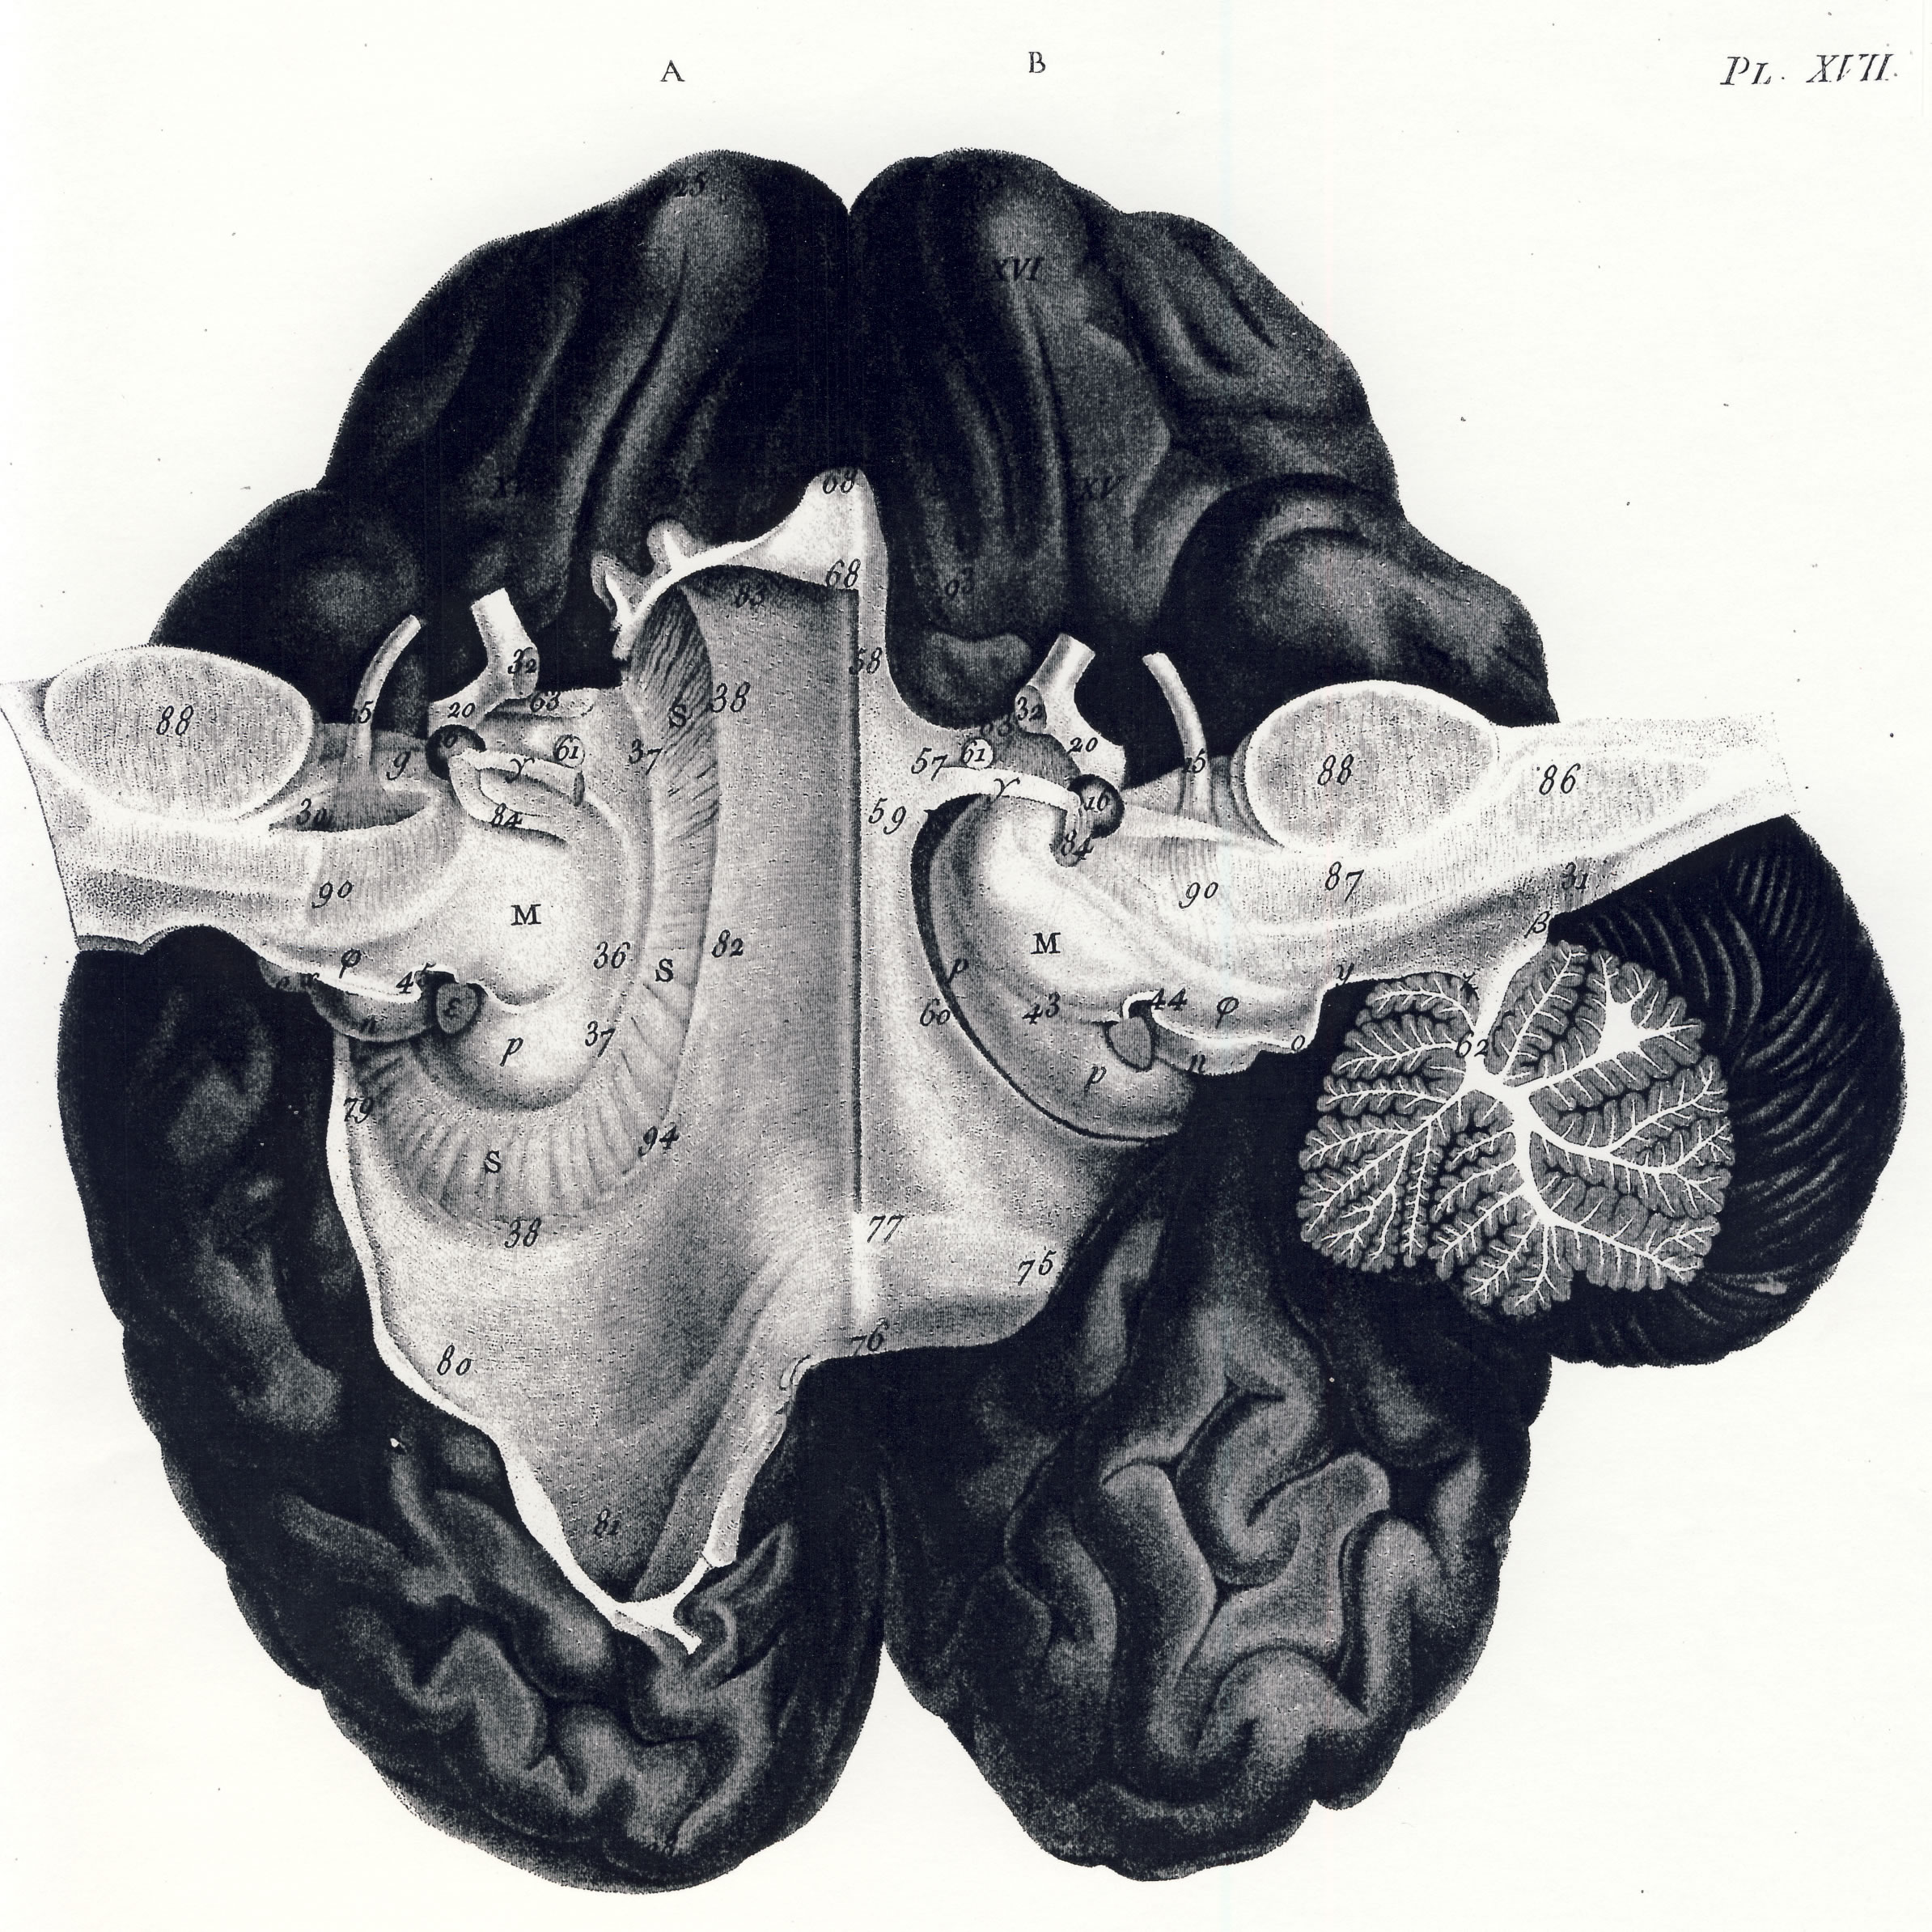

Gall: Plates

Gall, F. J. (1818). Anatomie et physiologie du système nerveux en général, et du cerveau en particulier, Avec des observations sur la possibilité de reconnoître plusieurs dispositions intellectuelles et morales de l´homme et des animaux, par la configuration de leurs têtes.

Librairie Grecque-Latine-Allemande, Vol. 3, I-XXXV u. 1-379 100 planches.